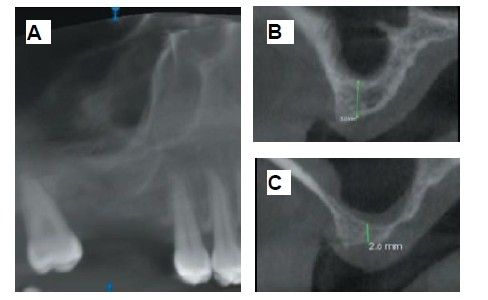

The medical history revealed no relevant medical or surgical antecedents, no known drug allergies, and no harmful habits. Intraoral examination revealed the absence of 1.6 and 1.7, and the presence of 1.8 and 4.8 (Figure 1). Radiographic examination using cone beam computed tomography (CBCT) revealed a residual height of 5.0 mm at 1.6, where an implant could be placed simultaneously, and 2.6 mm in the region of 1.7, making simultaneous implant placement with the lateral approach sinus elevation difficult (Figure 2).

Six months after the maxillary sinus elevation surgery, re-entry was performed for the placement of implants. A 3 x 7mm bone tissue biopsy was obtained using a trephine, and histomorphometric analysis was requested, revealing 30.56% vital bone (Figure 7). After the biopsy sample was taken, two bone level Naturactis implants from ETK® (ETK Implants S.L, Sant Boi de Llobregat, Spain) were placed with an insertion torque of 35 Ncm, and their correct positioning was confirmed in the immediate postoperative period by means of a periapical radiograph (Figure 8). Six months after the placement of the implants, the patient was able to attend for the second stage to place healing abutments. A verification CBCT was performed to assess the final bone height, revealing an increase of 4.2 mm in the region of 1.6 and 6.1 mm in the region of 1.7 (Figure 9).